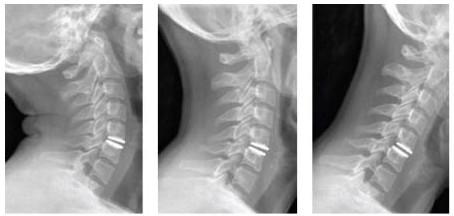

Ao lado, exemplo de prótese discal que preserva o movimento no segmento operado.

Aspecto radiográfico da prótese cervical e extensão, neutro e flexão.